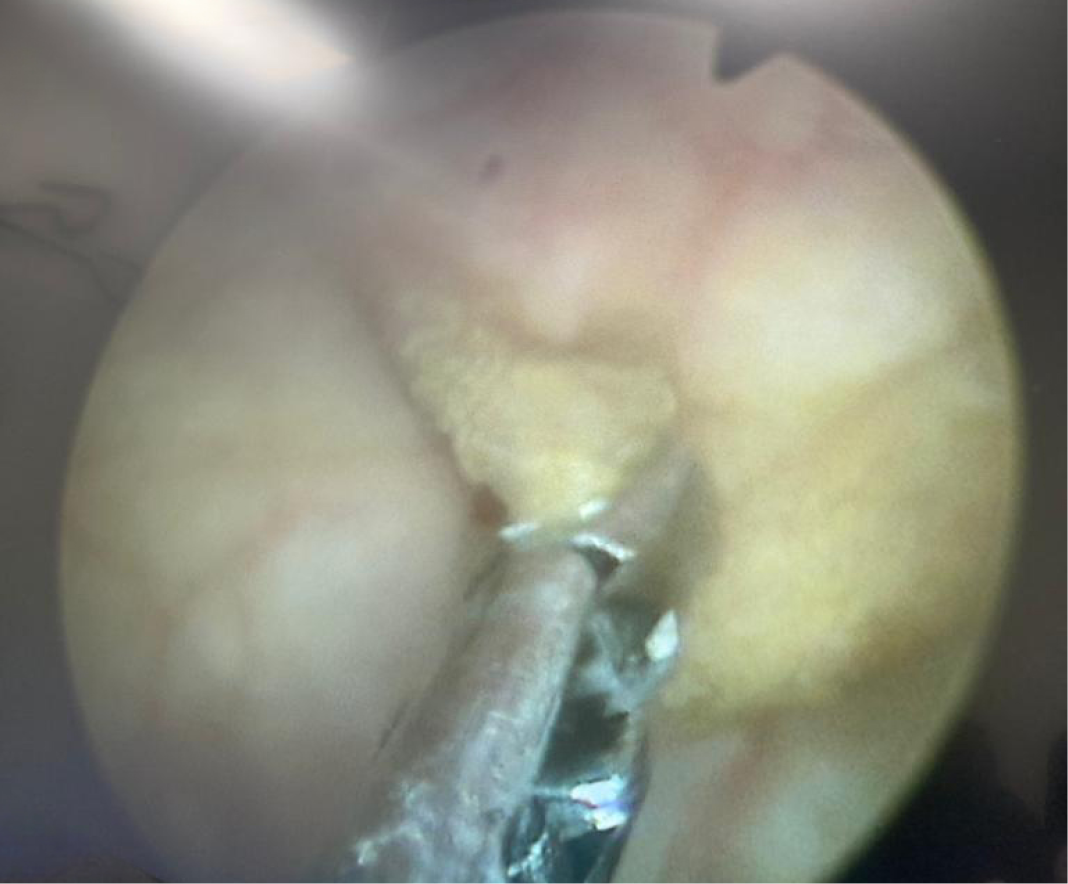

Solid oluşum olması üzerine üroloji ile konsülte edilen hastaya sistoskopi planlandı. Sistoskopide, mesane anterior superior duvarında yaklaşık 2×1 cm’lik papülonoduler lezyon görüldü (Resim 1-2). Lezyondan alınan biyopsi materyalinde lamina propriada parazitik infiltrasyon saptandı ve şiştozoma ile uyumlu olarak raporlandı (Resim 3). Eş zamanlı olarak mikrobiyoloji laboratuvarına gönderilen idrar örneğinde parazit yumurtaları tespit edildi (Resim 4). Hastaya praziquantel 2×40 mg/kg verildi. Bir ay sonra şikayetleri geçen hastanın kontrol idrar tetkikinde özellik yoktu. Sistoskopiyi kabul etmeyen hasta ülkesine döneceği için tekrar kontrole gelmedi.